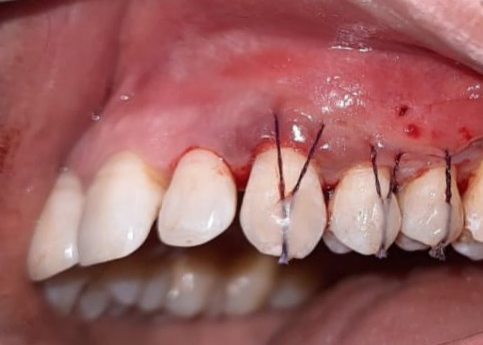

Gum Drop Technique With Titanium Prepared Platelet Rich Fibrin For The Treatment Of Multiple Gingival Recession : A Clinical Study

Investigators: Dr. Archita Datta, Dr. Arundeep Kaur Lamba, Dr.Shruti Tandon

Dental patients of all ages are increasingly concerned about their smile and overall appearance and are particularly unhappy when they have esthetic issues and dental pain associated with exposed roots. Gingival recession is the oral exposure of the root surface due to a displacement of the gingival margin apical to the cemento-enamel junction. Recession seen in healthy patients is mainly due to oral care that is “too much of a good thing” whereas recession seen in periodontally diseased patients is likely due to a chronic inflammatory process that may represent years of “doing too little of a good thing”. Regardless of the frequency & intensity of the oral hygiene, the symptom that brings periodontally healthy and unhealthy patients with recession to the dental clinic is a very unpleasant side effect common to both groups – dentin hypersensitivity.

This study is a prospective pre & post interventional study that involves 40 patients complaining of dentinal hypersensitivity along with at least 2 recession‐type defects affecting adjacent teeth in esthetic areas of the mouth. This technique is minimally invasive and it addresses the goals of root recession coverage with a biological approach to stimulate healing, reduce inflammation during healing, and provide long term stability of the repositioned gingival margin. A less invasive surgical approach has shown higher patient acceptance. Results observed on Patient centered outcomes i.e dentinal hypersensitivity &esthetic score have shown significant difference. The new biological approach of using T-PRF has provided a stimulus to growth factors encouraging new attachment of the gingival tissue to the root surface. This has led to identifying a new economical and readily available alternative to commercially available allografts. The technique has shown success and will work as a foundation step for future research on titanium prepared platelet rich fibrin (T-PRF) as an autologous graft for various therapeutic procedures.